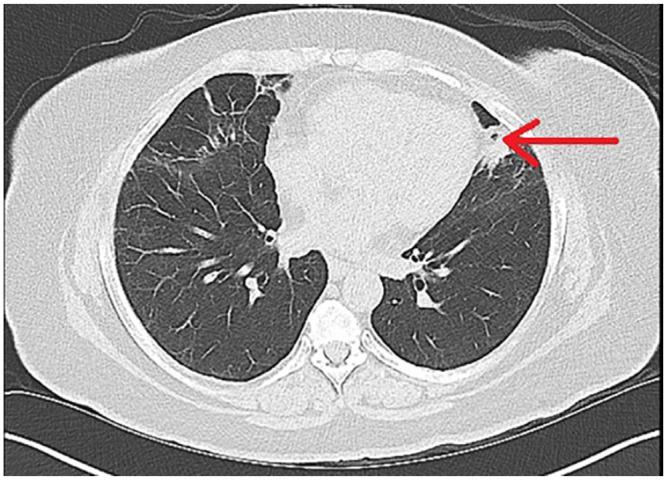

We present the case of a 56-year-old woman who was diagnosed with severe coronavirus disease 2019 (COVID-19) pneumonia complicated by severe acute respiratory distress syndrome who was intubated for 19 days. She recovered from COVID-19 after a month. A computed tomography (CT) scan of the chest, after a month, showed improved infiltrates with a small residual cavity within the lingula. A CT angiogram showed a more confluent density in the lingular portion on follow-up 2 months later. She developed intermittent hemoptysis after 3 months in December 2020, which persisted for almost 6 months, and CT of the chest showed the lingular nodular with resolution of the cavitation. She underwent bronchoscopy with bronchoalveolar lavage, confirming by galactomannan assay and histology showing branching hyphae. Once she started treatment with itraconazole, her hemoptysis resolved. The follow-up CT of the chest after 2 months of treatment did not show a cavity or a nodule in the lingula. Our patient developed invasive pulmonary aspergillosis (IPA) as a sequela of severe COVID-19 infection. COVID-19-associated invasive pulmonary aspergillosis (CAPA) is an underrecognized complication that needs to be investigated on whether prophylactic treatment is required. Our case also demonstrates that the diagnosis of IPA needs to be considered months after COVID-19 infection when a superimposed fungal infection can occur after a viral infection if the patient continues to have persistent symptoms.

我们报告了一例 56 岁女性,患有严重的 2019 年冠状病毒病(COVID-19)肺炎,并发严重急性呼吸窘迫综合征,气管插管 19 天。一个月后,她从 COVID-19 中康复。一个月后的胸部计算机断层扫描(CT)显示浸润有所改善,舌叶内有一个小残腔。两个月后随访的 CT 血管造影显示舌叶部分的密度更融合。2020 年 12 月,她在 3 个月后出现间歇性咯血,持续近 6 个月,胸部 CT 显示舌叶结节,空洞消失。她接受了支气管镜检查和支气管肺泡灌洗,半乳甘露聚糖检测和组织学检查均证实为分支状菌丝。一旦开始服用伊曲康唑治疗,她的咯血就得到了缓解。治疗 2 个月后的胸部 CT 随访未显示舌叶有空腔或结节。我们的患者因严重 COVID-19 感染而发生侵袭性肺曲霉病(IPA)。COVID-19 相关侵袭性肺曲霉病(CAPA)是一种认识不足的并发症,需要调查是否需要预防性治疗。我们的病例还表明,在 COVID-19 感染后数月,如果患者持续存在症状,可能会发生真菌感染,需要考虑 IPA 的诊断。